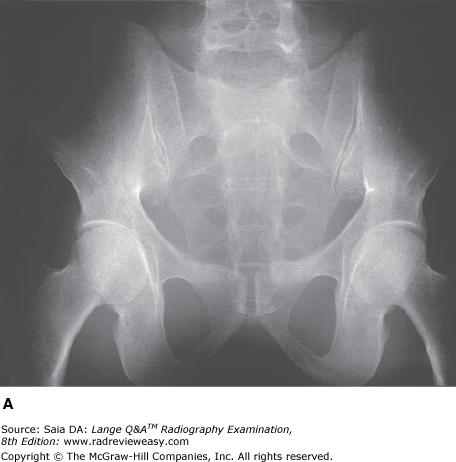

Which of the following statements is (are) true regarding the images below?

- Image A was made using a higher kilovoltage than image B.

- Image A was made with a higher-ratio grid than image B.

- Image A demonstrates shorter-scale contrast than image B.

A 1 only

B 1 and 2 only

C 2 and 3 only

D 1, 2, and 3

-Image A was made using 80 kV at 75 mAs; image B was made using 100 kV at 18 mAs; all other exposure factors remained the same. As kilovoltage is increased, the percentage of scattered radiation relative to primary radiation increases—hence, the grayer appearance of image B. Use of optimal kilovoltage for each anatomic part is helpful in keeping scatter to a minimum. The production of scattered radiation also will be limited if the field size is as small as possible. A grid is the most effective way to remove scattered photons from those exiting the patient. Grids are designed to selectively absorb scattered radiation while absorbing as little of the useful beam as possible. Images produced with higher-ratio grids are likely to evidence the effect of less scattered radiation than those made with lower-ratio grids.